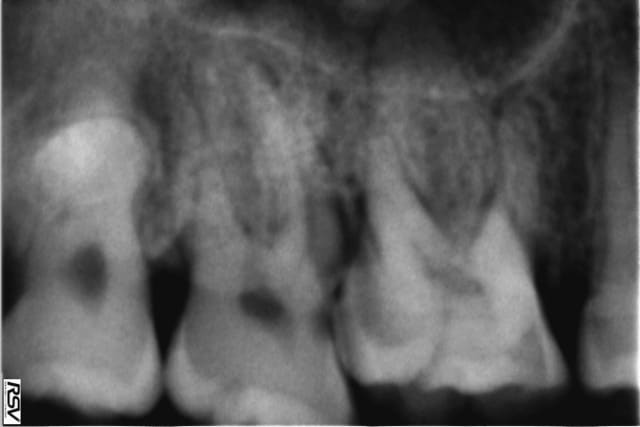

Voici la radio de la 17, évidemment que la dent est conservable...

La dent est passée en pulpite donc plus de question à se poser si ce n'est du pronostic à long terme.

La carie est plus petite que ce que tu laissais imaginer!

C'est pas exactement ce que montre ton cliché... Peut-etre que tu devrais reevaluer le pronostic. En tous cas ne laisse pas trainer: même si les douleurs disparaissent, ta 16 finira par en beneficier.

La poche? le cliché es flou ! mes yeux??